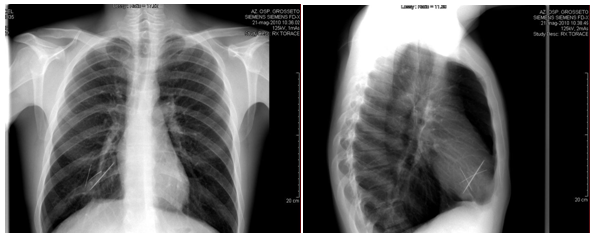

The chest roentgenogram at admission showed the presence of three foreign bodies (Figure 1A & 1B) into an area of chronic inflammatory disease in the right middle lobe of the lung. A successive bronchoscopy was negative for intrabroncheal foreign bodies, but showed the presence of coagulated blood in the middle bronchus of the right lung.

Figure 1 A & B The chest roentgenogram at admission showed the presence of three foreign bodies (Figure 1A-B) into an area of chronic inflammatory disease in the right middle lobe of the lung.